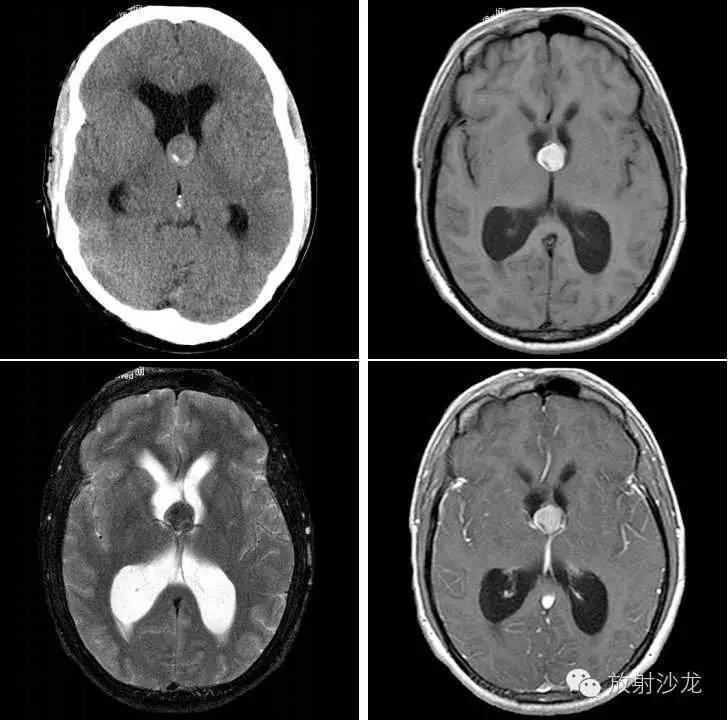

男性,25岁

主诉:头疼进行性加重2个月

入院行CT及MRI检查

临床诊断:颅内占位性病变

影像检查结果

CT:第三脑室前方见一圆形稍高密度影,右后方可见钙化,边缘清晰,双侧侧脑室扩张。

MRI:第三脑室前方靠近孟氏孔区见一类圆形异常信号,T1WI呈高信号,T2WI呈低信号,增强扫描未见明显强化;双侧脑室扩张,中线结构居中。